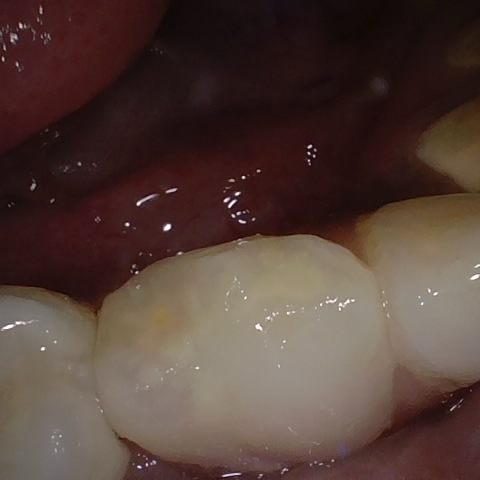

Annotated as "Good"